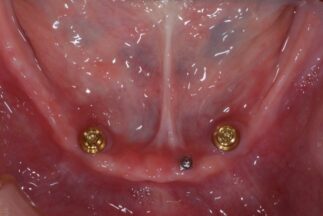

インプラント埋入後の下顎咬合面観

-